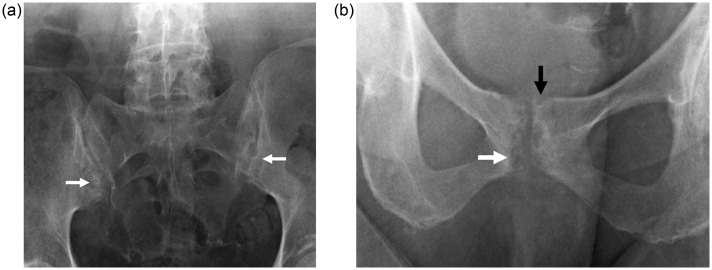

在这个病例报告中,我们描述了一个“罕见”的轴性痛风性关节病,患者是一位69岁的女性,患有双侧坐骨神经痛,并通过常规x线摄影、CT扫描、磁共振成像、骨显像和PET-CT进行了全面评估。轴性痛风关节病应包括在慢性腰痛的鉴别诊断中,主要是当存在痛风的几个危险因素时。

In this case report, we describe an "uncommon" case of axial gouty arthropathy in a 69-year-old woman with bilateral sciatica that was thoroughly evaluated with conventional radiography, CT scan, magnetic resonance imaging, bone scintigraphy, and PET-CT. Axial gouty arthropathy should be included in the differential diagnosis of chronic low back pain, mainly when several risk factors for gout are present.